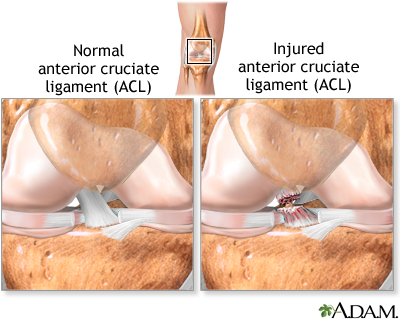

An anterior cruciate ligament injury is the over-stretching or tearing of the anterior cruciate ligament (ACL) in the knee. A tear may be partial or complete.

- Anterior cruciate ligament (ACL) is in the middle of the knee. It prevents the shin bone from sliding out in front of the thigh bone.

Most ACL tears occur in the middle of the ligament, or the ligament is pulled off the thigh bone. These injuries form a gap between the torn edges, and do not heal on their own.